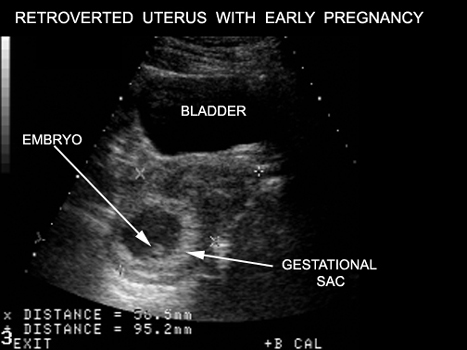

Image Atlas of Normal Pregnancy |